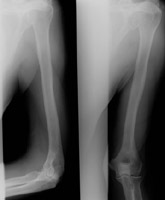

- Click on the image for a larger versionBAP and lateral radiographs of the humerus. One year prior, the lytic lesion is not apparent.